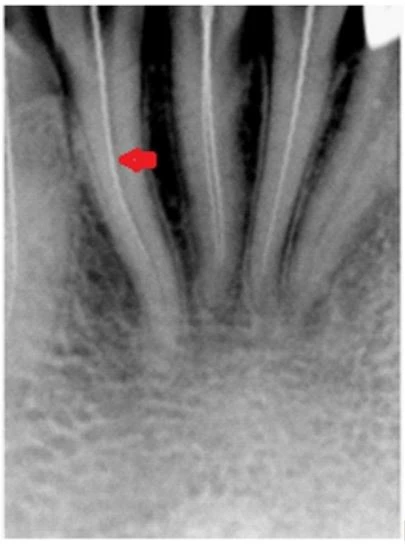

– Nhìn trên phim X-quang có 1 đường song song với lamina dura (mũi tên màu đỏ). Dấu hiệu này gợi ý tiết diện chân răng hình số 8(hình 1.1).